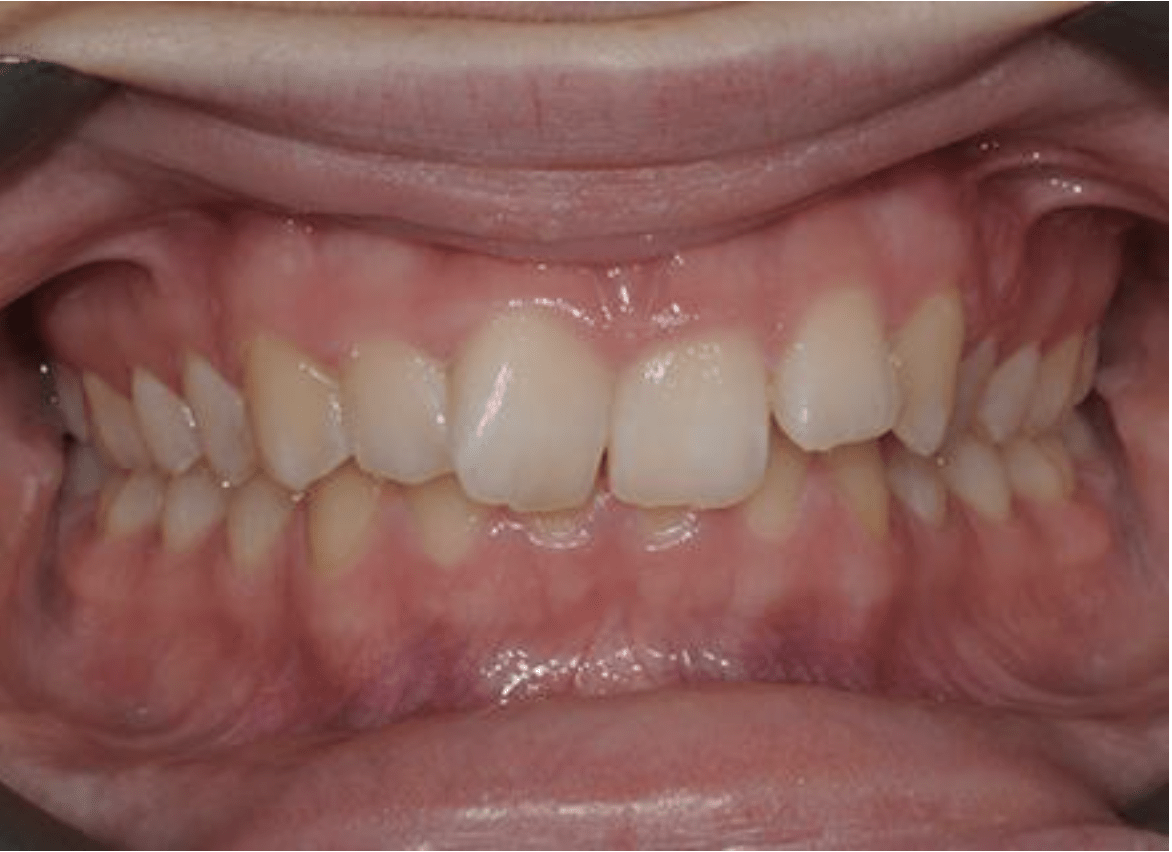

In this case, the upper incisors had a pushed back appearance and they were twisted. the smile was narrow – when the patient smiled the sides of the smile were in shadow. we used clear brackets to gently untwist and straighten the front teeth while widening the upper arch/jaw to broaden the smile. this patient was beaming for the first time in just 12 months.